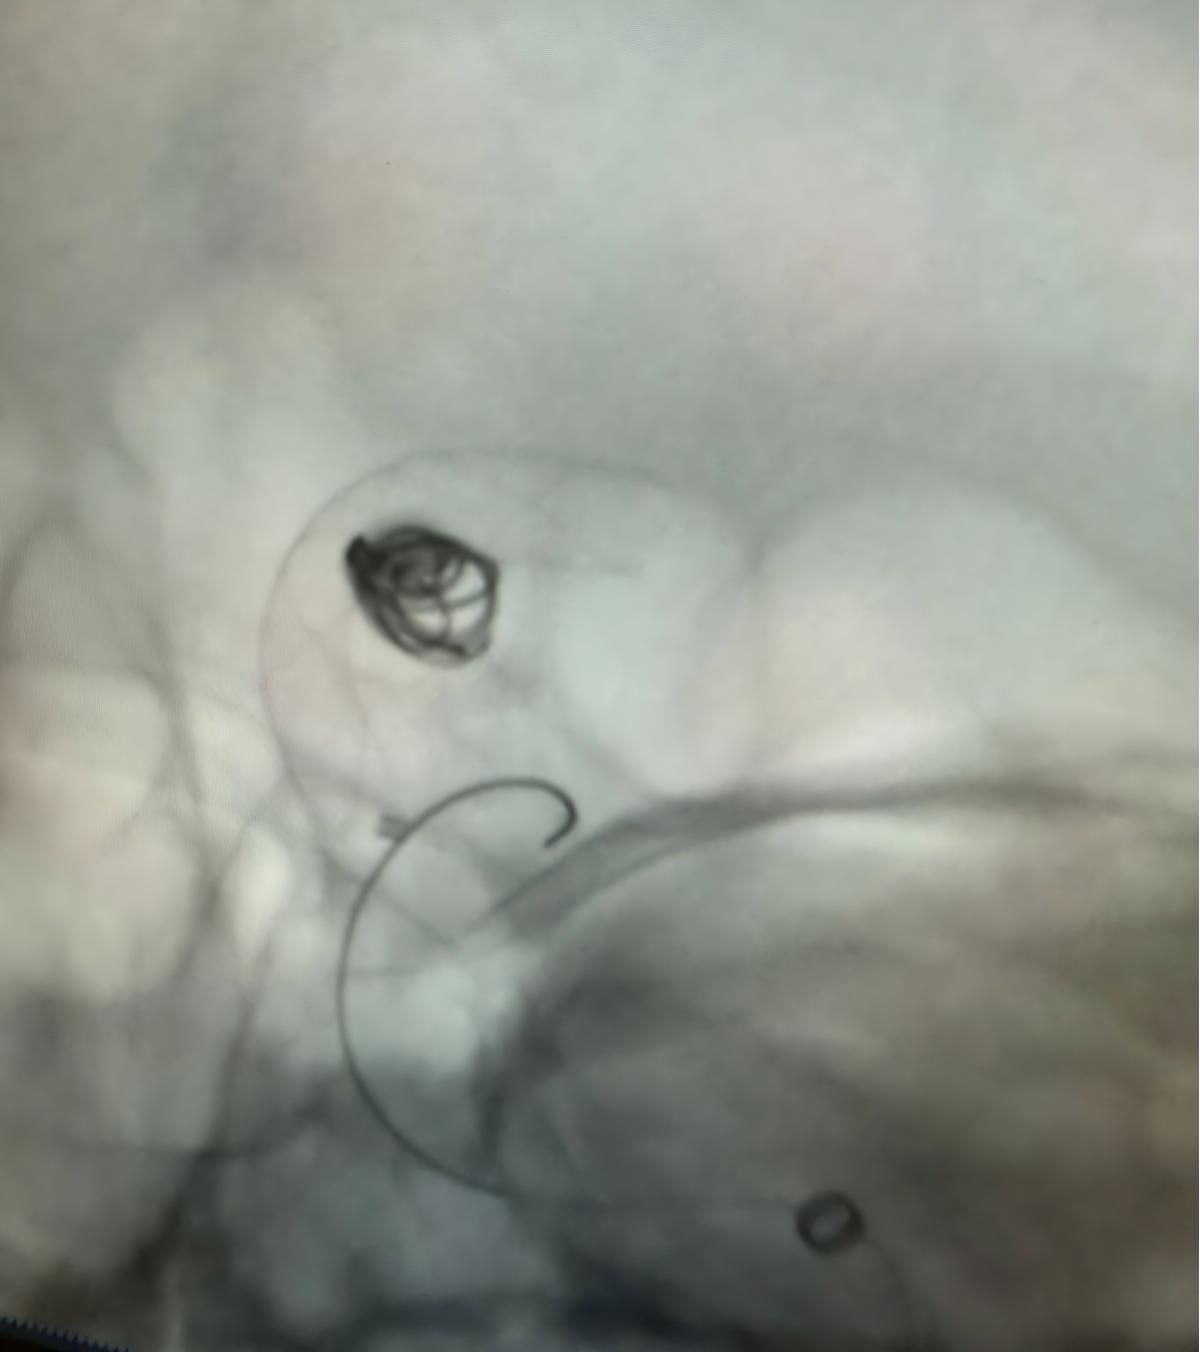

Siamo lieti di condividere una recente procedura di successo presso Clínica Alma Mater, Medellín, eseguita dal Dr. Jorge Mutis.

Il trattamento ha utilizzato la Nuva®Deviatore di flusso (TJED-D 5.0-14), Perdenser®Bobina 3D e Fepass®Microcatetere (TJMC18 Plus) per un aneurisma dell'arteria comunicante posteriore.

Il dottor Mutis ha evidenziato l'eccellente visibilità del dispositivo e ha notato che il recupero è stato regolare. Ha espresso grande soddisfazione per l'esito finale.